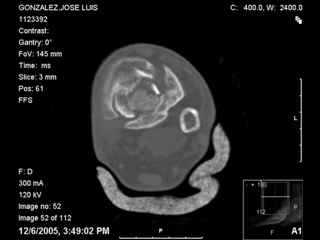

A 56 year old laborer fell off a wall approximately 5 months ago. He sustained an open pilon fracture. He was treated with debridement and external fixation. After he was treated for 4 months, the external fixator was removed.

I have attached his x-rays. I have also attached an WMV movie file of his axial CT (if you are unable to view this, I can post an MPEG file).